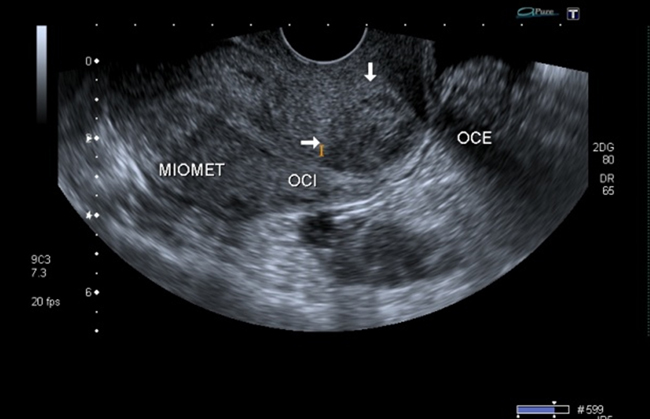

A la paciente se le realizó una prueba en sangre para cuantificar la fracción beta de la gonadotrofina coriónica humana (Abbott Laboratories. Architect.B-hCG Total), que se reportó en 31.819 mUI/ml. También se le tomó una ecografía endovaginal (Toshiba-Xario XG) que mostró la presencia de útero con medidas de 72 × 52 × 54 mm con un cuello de 35 mm con orificio interno cerrado. El endometrio midió 18 mm, sin evidencia de saco gestacional intrauterino y en la región ístmica y cervical, por debajo de las arterias uterinas, se encontró un saco gestacional de 30 mm con presencia de embrión único de 20,6 mm sin presencia de actividad cardiaca fetal (figuras 1 a 4).

Figura 1 Presencia de cavidad uterina vacía, con endometrio sin presencia de saco gestacional. Presencia de saco gestacional cervical

Figura 2 Presencia de cavidad endometrial vacía (flecha amarilla). Embarazo extrauterino cervical con embrión único sin actividad cardiaca (flecha blanca)

Figura 4 Orificio cervical interno cerrado (flecha amarilla), debajo del cual se evidencia la implantación del saco gestacional en la mucosa cervical